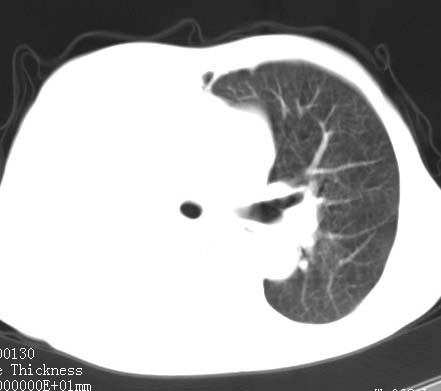

病人女 60岁 咳嗽 气促十余天,大叶性肺炎.

右肺上下叶均见 大片状密度增高影,边界清晰,其内可见支气管充气征,气管支气管通畅。纵膈略向右移位,其内无肿大淋巴结影。首先考虑炎性病变。不排除一些特异性的炎症。不知道发烧吗??wbc高吗??建议治疗后复查!!